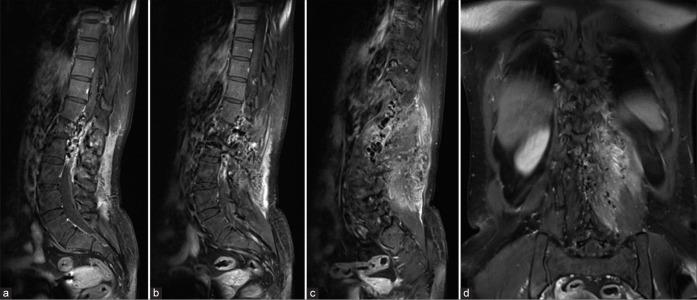

A 42-year-old woman presented with intermittent low back pain for 6 months. Magnetic resonance imaging of the thoracolumbar spine incidentally found clusters of spinal vascular malformations involving spinal cord, vertebral bodies, epidural space, and paraspinal muscles. There was no sign of venous congestion. Magnetic resonance angiography and spinal angiography revealed intradural spinal cord arteriovenous malformation (SCAVM) at the level of T10-11 and extradural high-flow osseous arteriovenous fistula. Due to asymptomatic SAMS and a high risk of anterior spinal arterial compromise during treatment, conservative treatment was considered in our patient. Spinal angiography obtained 8 years after initial angiography demonstrated significant regression of extradural component of SAMS and stable intradural SCAVM.

一名42岁女性出现间歇性腰痛6个月。胸腰椎磁共振成像偶然发现累及脊髓、椎体、硬膜外间隙和椎旁肌肉的脊髓血管畸形簇。无静脉淤血迹象。磁共振血管造影和脊髓血管造影显示T10 - 11水平的硬脊膜内脊髓动静脉畸形(SCAVM)和硬膜外高流量骨动静脉瘘。由于患者为无症状性SAMS且治疗期间存在脊髓前动脉受损的高风险,我们的患者考虑采取保守治疗。初次血管造影8年后进行的脊髓血管造影显示SAMS的硬膜外成分显著消退,硬脊膜内SCAVM稳定。